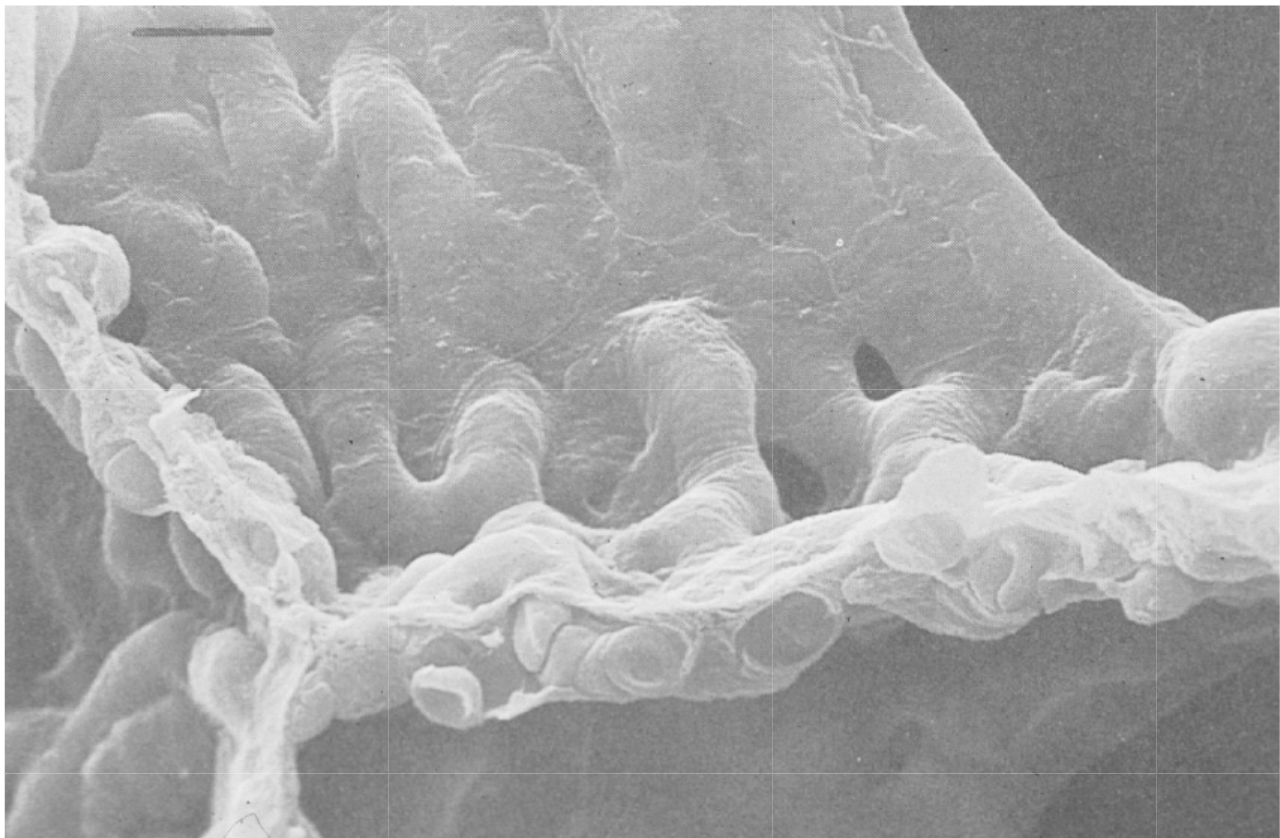

Electron micrographs of the collagen fibre network of rat lung at low lung volume (A) and when fully inflated (B).12 Note the folded, zigzag shape of the collagen at low lung volume in (A). Source: (Photograph from Professor Ohtani. Reproduced by permission of Archives of Histology and Cytology.)